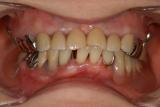

包括的歯科診療パート2 | ||

| 50代の女性の患者さんです。お口の中を全体的に治療させていただきました。インプラントも使用していますが私達、歯科医の究極目的は機能・審美的な口腔内を育成・構築・保全して行くことだと思っています。インプラントはあくまでもそのための手段にすぎません。手段の目的化ではいけません。 | ![]() |

【術前】 |

【術後】 |